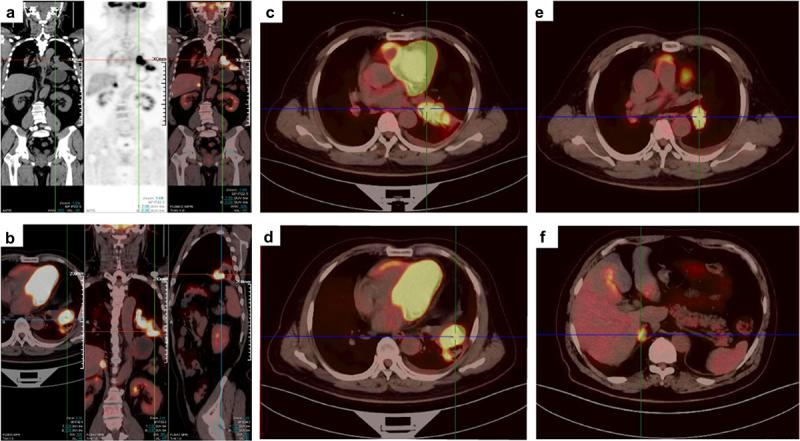

This case study details an innovative conversion therapy strategy in a 58-year-old Asian male with baseline stage cTNM advanced lung squamous cell carcinoma (SCC) harboring a rare exon 20 insertion mutation with concurrent high PD-L1 expression who achieved a pathologic complete response (pCR) after preoperative immunotherapy plus chemotherapy. The patient initially presented with coughing and bloody sputum and was comprehensively diagnosed via PET/CT scanning, bronchoscopic biopsy and next-generation sequencing. After four cycles of platinum‒paclitaxel chemotherapy plus immunotherapy with pembrolizumab (a PD-1 blockade), significant primary tumor shrinkage and the disappearance of oligometastasis in the right adrenal gland were discovered via CT scans. The subsequent salvage lung surgery resulted in a pCR, and the patient continued postoperative maintenance immunotherapy. No evidence of disease relapse or immune-related adverse events occurred after a post-surgery follow-up time of 9.4 months. This case highlights the potential value and challenges of immunotherapy plus chemotherapy as conversion therapy strategy in treating patients with non-small cell lung cancer (NSCLC) harboring rare exon 20 insertions.

本病例研究详细介绍了一种针对一名 58 岁亚洲男性的创新转化治疗策略。该患者基线时患有晚期 cTNM 肺鳞状细胞癌(SCC),携带罕见的外显子 20 插入突变,同时 PD-L1 表达水平较高。该患者在接受术前免疫治疗联合化疗后获得了病理完全缓解(pCR)。该患者最初表现为咳嗽和咯血,并通过 PET/CT 扫描、支气管镜活检和下一代测序进行了全面诊断。在接受了四个周期的铂类紫杉醇化疗联合免疫治疗(pembrolizumab,一种 PD-1 阻断剂)后,通过 CT 扫描发现原发肿瘤明显缩小,右侧肾上腺的寡转移灶消失。随后进行的挽救性肺手术获得了 pCR,患者继续接受术后维持性免疫治疗。在术后随访 9.4 个月后,未发现疾病复发或免疫相关不良事件。本病例强调了免疫治疗联合化疗作为治疗携带罕见外显子 20 插入的非小细胞肺癌(NSCLC)患者的转化治疗策略的潜在价值和挑战。